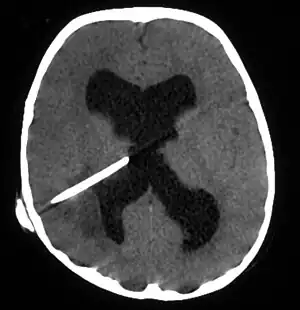

Brain abscess in a person with a CSF shunt.[1]